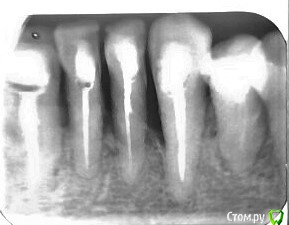

Просто несколько работ, достаточно рутинных

post-52119-0-20295000-1577291406_thumb.jpg

post-52119-0-72851000-1577291413_thumb.jpg

post-52119-0-99190300-1577291423_thumb.jpg